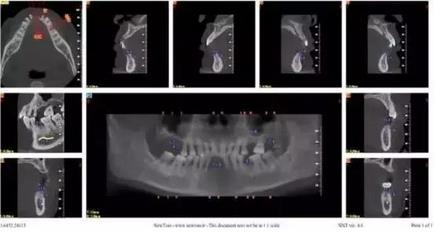

拔牙前CT截圖